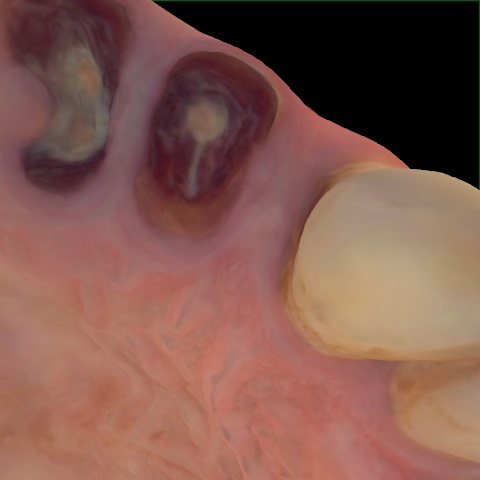

Incorrect Quality Level

The reference annotation for this image is

None

.

Please select the correct quality level.

Annotated as "Good"